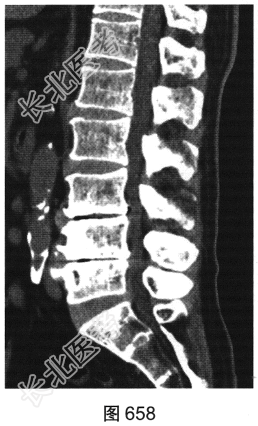

- 多项选择题2.[提示]患者行腰椎X线及CT检查,见图655~图659。患者有哪些阳性影像学表现( )

A、椎间盘“真空现象”

B、腰椎前滑脱

C、椎间盘膨出、突出

D、腰椎轻度侧弯

E、椎小关节骨质增生硬化

F、腰椎间隙变窄

- 多项选择题4.综合X线、CT和MRI图像,该患者有以下哪些腰椎退变征象( )

A、终板炎

B、腰椎间盘突出

C、许莫结节

D、黄韧带肥厚

E、腰椎管狭窄

F、腰椎间盘脱出,髓核游离